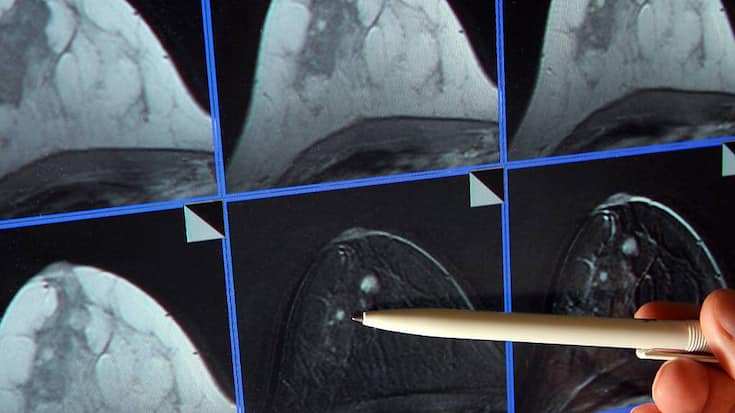

Le cancer du sein occupe déjà une position importante dans la franchise oncologique du géant pharmaceutique rhénan. (archive) KEYSTONE/DPA dpa-Zentralbild/Z1009/_JAN-PETER KASPER